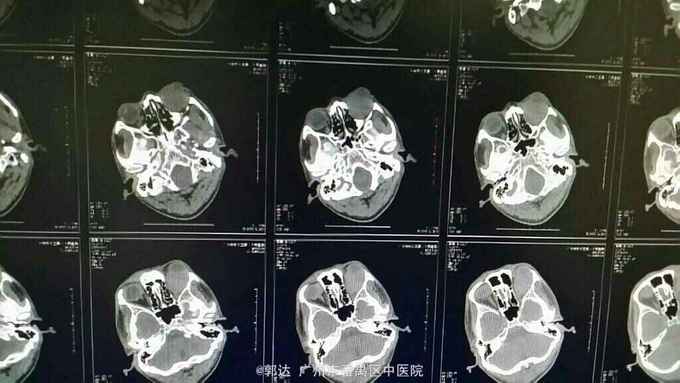

患者男性,41岁。左眼反复眼睑肿胀2年,加重伴眼球突出1月余。患者曾余当地医院行CT检查提示左眶病变,考虑血肿与占位性病变。诊断为左眶蜂窝织炎并予抗感染治疗,无明显好转。

检查:患者视力不配合,左眼眼球突出伴向外偏斜,左眼眶压T+1,左眼下睑红肿,下睑可触及肿块,大小约2*3cm,质地中,边界不清伴压痛,不可活动,余查体未见明显异常。眼部超声:左眼玻璃体混浊、视网膜脱离、脉络膜脱离声像。左眼眶实质性占位性病变声像。眼眶MRI提示左眼球后、右侧眼眶内上方多发占位性病变,考虑1、炎性假瘤2、淋巴瘤

诊断:双眼眶肿物、左眼陈旧性视网膜脱离 治疗:全麻下行眼眶肿物切除+周围神经嵌压松解+眶隔修补术

随访:术后病理为左眼眶非霍奇金B细胞淋巴瘤。 讨论:患者以双眼眶肿物为特征,多见为淋巴瘤、炎性假瘤,两者在临床和影像上均类似,最后鉴别需要病理证实。术后应辅以全身化疗。